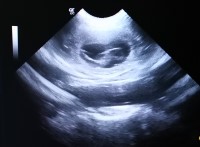

31.08.2021 (25. Trachtigkeitstag) |

Zwischen dem 18 . – 20 . Tag nisten sie sich

dann ein und die Ausbildung der Plazenta beginnt

Am 20. Tag besitzt nun auch jeder Embryo seinen

festen Platz.

Mit 25 Tagen sind die

Embryonen ca. walnussgroß

Wir waren beim Ultraschall und sind tragend!!

Wir konnten viele Fruchtblasen sehen. Auf

dem Foto gut zu erkennen. Die Fruchtblase mit

dem kleinen Welpen drinnen.

Freu, freu

Wenn alles gut läuft, dann kommen die Kleinen um

den 6. Oktober rum zur Welt.

Der

Bauchumfang ist bei 64 cm |